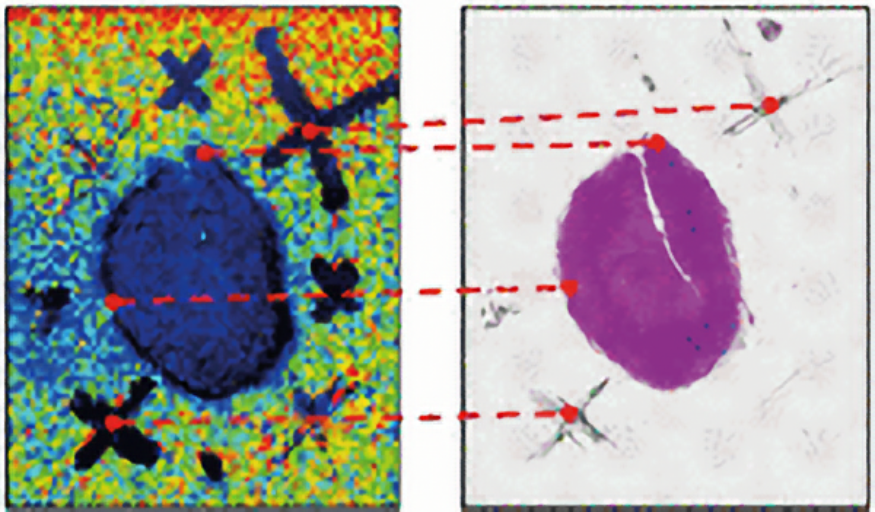

Galaxy Image Analysis: MALDI and Histology Data

Galaxy Docker ParaView

GitHub: https://github.com/BMCV/docker-paraviewweb

Now maintained at: https://github.com/BMCV/docker-paraview